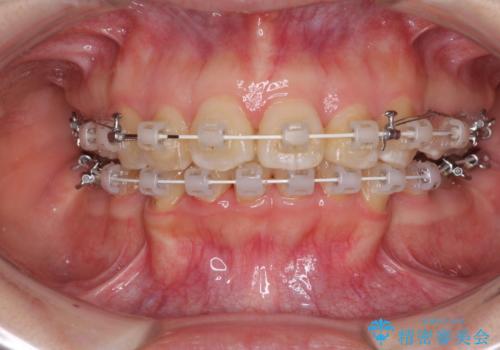

- 矯正装置

- 審美装置

- 口元の閉じにくさと、前歯のでこぼこの歯並びを気にして来院された患者様です。

口元を積極的に引っ込めるために、上下左右の小臼歯計4本を抜歯することとしました。

咬み合わせが深く、咬合力強いため、補助装置を使用しながら積極的に口元を下げることとしました。